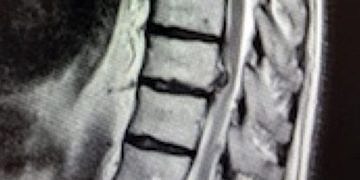

Bel fıtığı, bel ve bacak ağrılarının en yaygın nedenidir; insanların çoğu bel fıtığı sorunu yaşar. Fizik tedavi ve ameliyat en...

Sırt bölgesinde 12 omurun bulunduğu omur arasında bulunan kıkırdağın aniden dışarı fırlaması sonucu omuriliğin direkt basısına neden olan fıtık grubudur. Nadir görülürler ama karakteristik bir semptomatolojisinin olmaması...